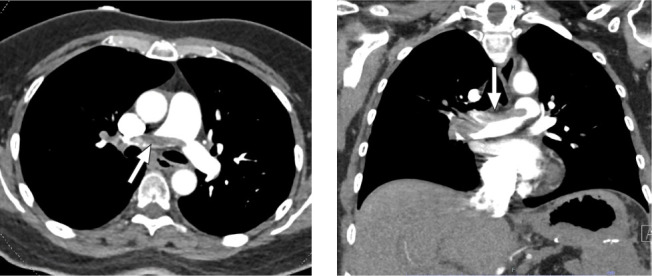

高危肺栓塞(PE)是一种与高死亡率相关的复杂临床实体。超声辅助导管引导溶栓通常用于中危肺栓塞,而对于高危肺栓塞,尤其是大出血风险较高的患者,超声辅助导管引导溶栓可能是一种可行的治疗方法。本报告描述了一例成功使用超声辅助导管引导溶栓治疗高危 PE 的病例,患者为女性,胃腺癌广泛腹膜转移。此外,还提供了文献中利用超声辅助导管引导溶栓治疗高危 PE 的其他实例。

High-risk pulmonary embolism (PE) is a complex clinical entity associated with high mortality rates. Ultrasound-assisted, catheter-directed thrombolysis, typically used for intermediate-risk PE, may be a viable treatment approach for high-risk PE, particularly in patients at increased risk for major bleeding. This report describes a case in which ultrasound-assisted, catheter-directed thrombolysis was successfully used to treat high-risk PE in a female patient with extensive peritoneal metastases from gastric adenocarcinoma. Other examples from the literature, in which ultrasound-assisted, catheter-directed thrombolysis was used to treat high-risk PE, are also provided.